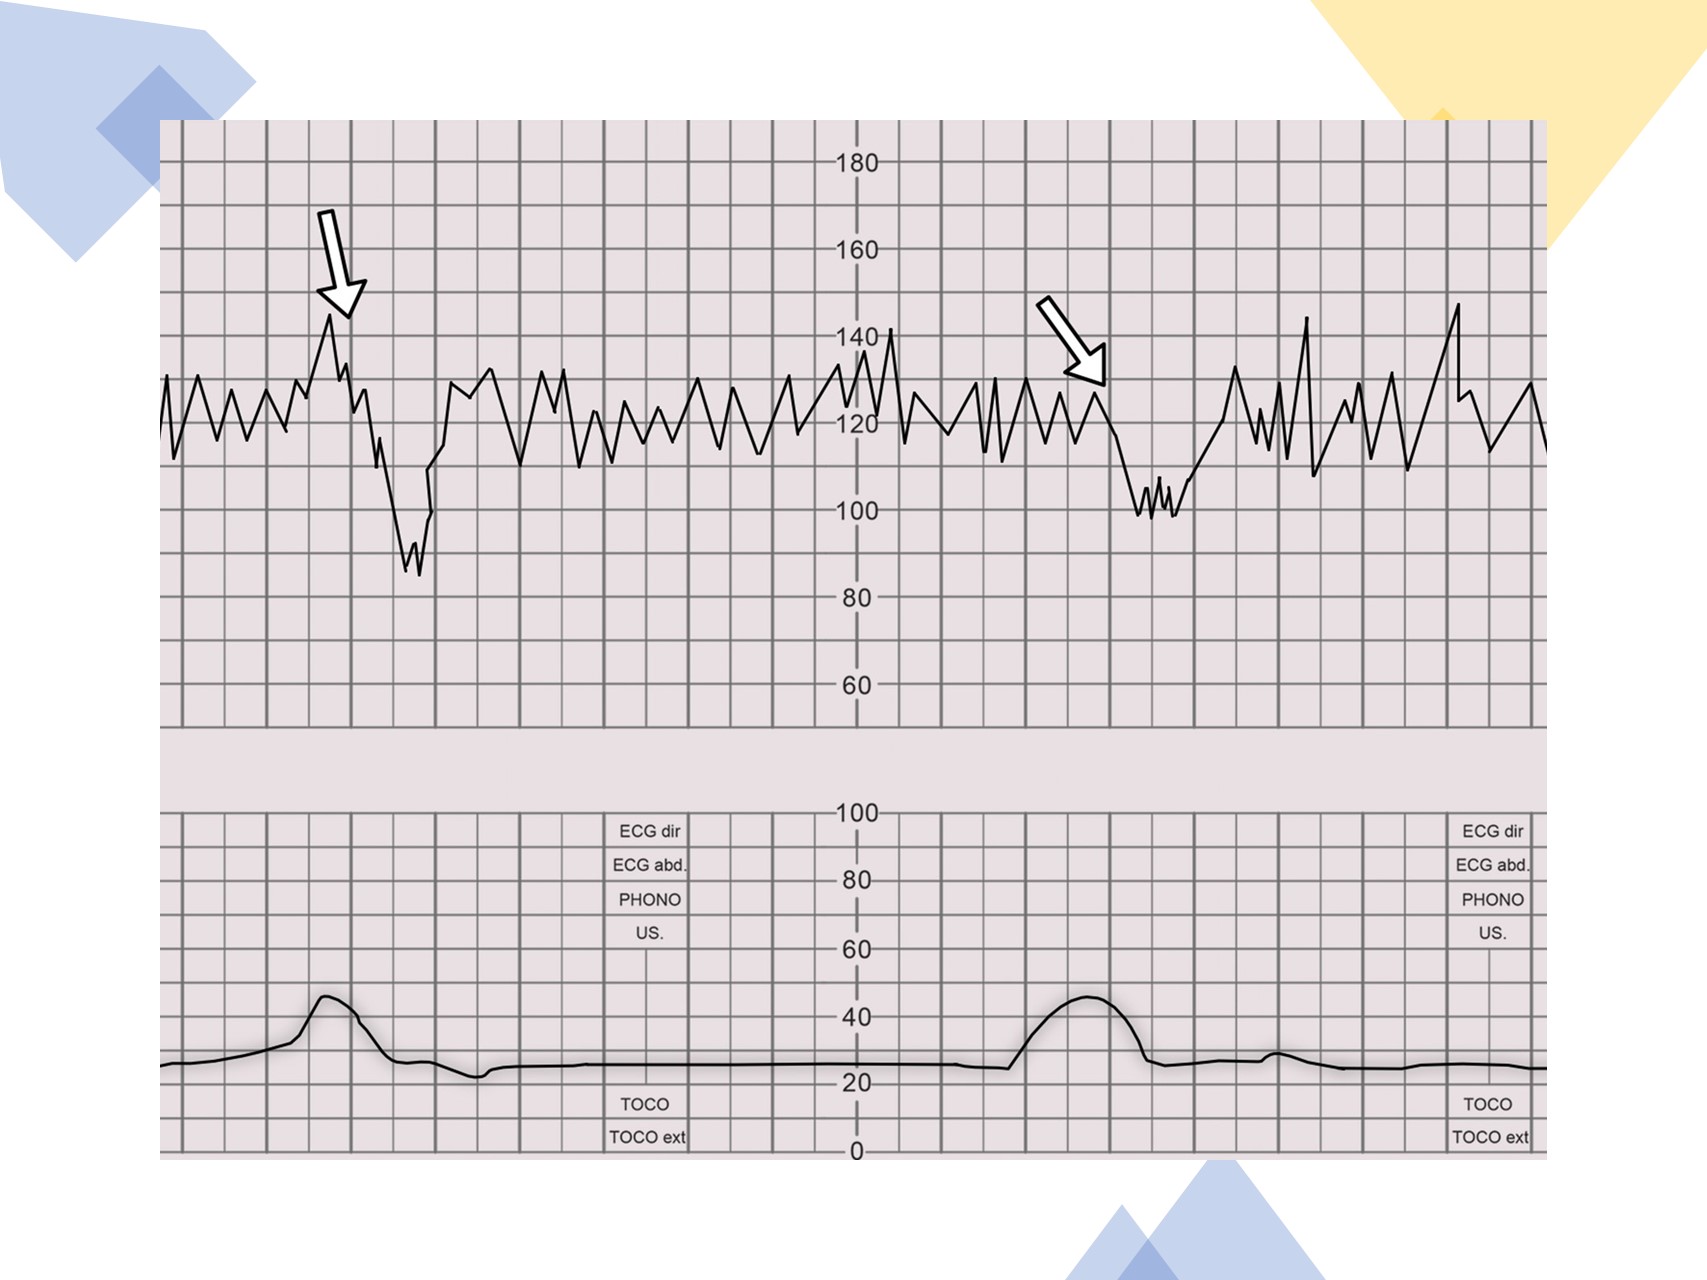

- Pozitivan - pozitivan (patološki) test ima kasne deceleracije nakon ≥50 posto kontrakcija. Test je pozitivan čak i ako je frekvencija kontrakcije manja od tri u 10 minuta.

- Negativan - negativni (normalan) test nema kasnih deceleracija ili značajnih varijabilnih usporavanja.

- Dvosmislen – dvosmislen test ima povremene kasne deceleracije ili značajne varijabilne deceleracije.

Pozitivan (patološki) CST ukazuje na prolaznu hipoksemiju fetusa tijekom kontrakcije maternice i može biti indikacija za porođaj, ovisno o razvoju događaja. Daljnja procjena može uključivati biofizički profil (BPP) i, kod zastoja rasta fetusa, doplerske protoke. CST s varijabilnim deceleracijama sugerira kompresiju pupčane vrpce do koje može doći zbog oligohidramnija.